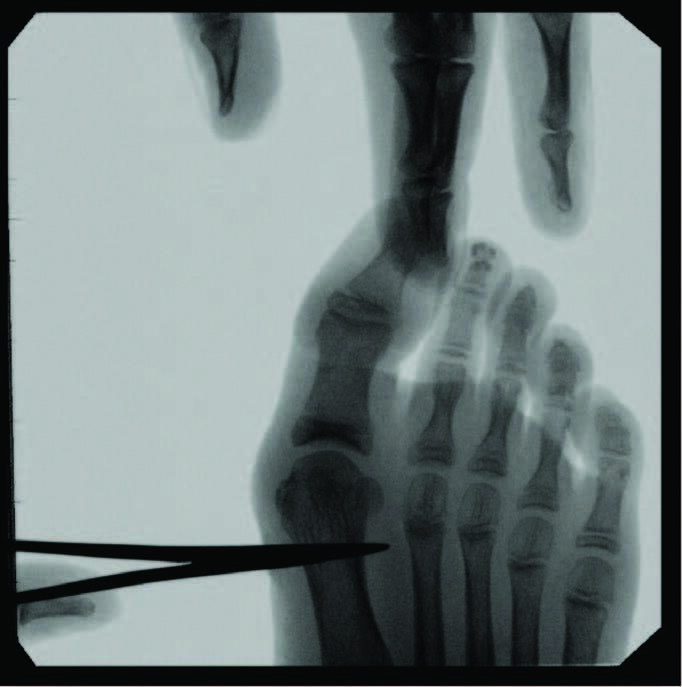

Predictors of juvenile HAV severity, in addition to subtalar joint pronation, include: rounding of the first metatarsal head; an atavistic cuneiform; a hypermobile or long first ray; and a high metatarsus primus adductus angle.4 Additional pes planus-related radiographic measurements include an increased first intermetatarsal angle, reported in 26.6 percent of adolescents and an increased metatarsus primus varus angle in 8.1 percent.5 Anatomic abnormalities such as Achilles equinus contractures, digital contractures, syndactyly, metatarsus adductus, hereditary exostoses, and congenital hip dislocation may need attention for long-term successful HAV treatment. Other considerations include brachymetatarsia, where a shortened lesser metatarsal leads to an abnormal transverse metatarsal parabola, allowing more lateral deviation of the hallux and increased metatarsus varus angle due to soft tissue balancing effects.

Harb and team reviewed patient satisfaction and radiological outcomes of more traditional methods of juvenile HAV correction, including proximal metatarsal, shaft, and distal procedures from nine different studies.1 Complications included infection (two percent), postoperative pain (11.9 percent), recurrence (eight percent), non-union (0.5 percent), metatarsalgia (0.5 percent), scar hypersensitivity (4.5 percent), and development of complex regional pain syndrome (0.5 percent). The overall revision rate was four percent due to non-union, recurrence, and dissatisfaction with cosmesis.1 One study also focused on the MIS approach, which reported undercorrection (10 percent). The review concluded that as fixation methods and techniques improve in surgical correction of juvenile HAV, patient satisfaction and clinical outcomes will only continue to improve. Also, they noted that anatomic variations influenced by skeletal maturity continues to influence surgical timing.1

Although minimally invasive hallux valgus surgery is a more modern technique, especially for the pediatric population, it still relies, in my experience, on AO principles of fracture fixation, including anatomic reduction in the first intermetatarsal and hallux abductus angles, stable fixation, preservation of blood supply, and early active mobilization. I find the percutaneous approach allows the reduction of a wide range of mild to severe radiographic angles and preservation of blood supply. In a study of minimally invasive bunion procedures, surgeons achieved up to a 12.5 degree correction of the first intermetatarsal angle and reported a 5.3 percent reoperation rate. The study was from a surgeon’s first 94 MICA procedures, and the author challenged the previously reported steep learning curve, citing low complication rates and ease of reproducibility.13

In a study comparing MIS to distal chevron metatarsal osteotomy bunion correction in a population of young females, there were no statistically significant outcomes in postoperative radiographic measurements of hallux valgus angle, DMAA, sesamoid position, first metatarsal length, and relative second metatarsal length.15 Clinical scores significantly increased postoperatively in both groups, with higher cosmesis satisfaction rates and a shorter operative time in the MIS group. This study found that the most significant complication in the MIS group was revision due to osteotomy site irritation occurring about three months postoperatively, while deformity correction was necessary two years postoperatively in the chevron group.15

Kaufmann and colleagues compared five-year outcomes of open distal metatarsal chevron osteotomies to a minimally invasive approach, finding comparable satisfaction as well as radiographic and clinical outcomes in both groups.16 More recently, Neufeld and team reported that the minimally invasive chevron and Akin (MICA) procedure achieves reproducible significant correction and high patient satisfaction with early weight-bearing and fast pain score improvement.13 They noted a 5.3 percent reoperation rate due to hardware removal, debridement, and neurolysis, finding no significant increase in nerve injury between the MICA and open procedure groups. The authors also noted significant deformity correction is possible with the third-generation approach of utilizing two bicortical screws.13